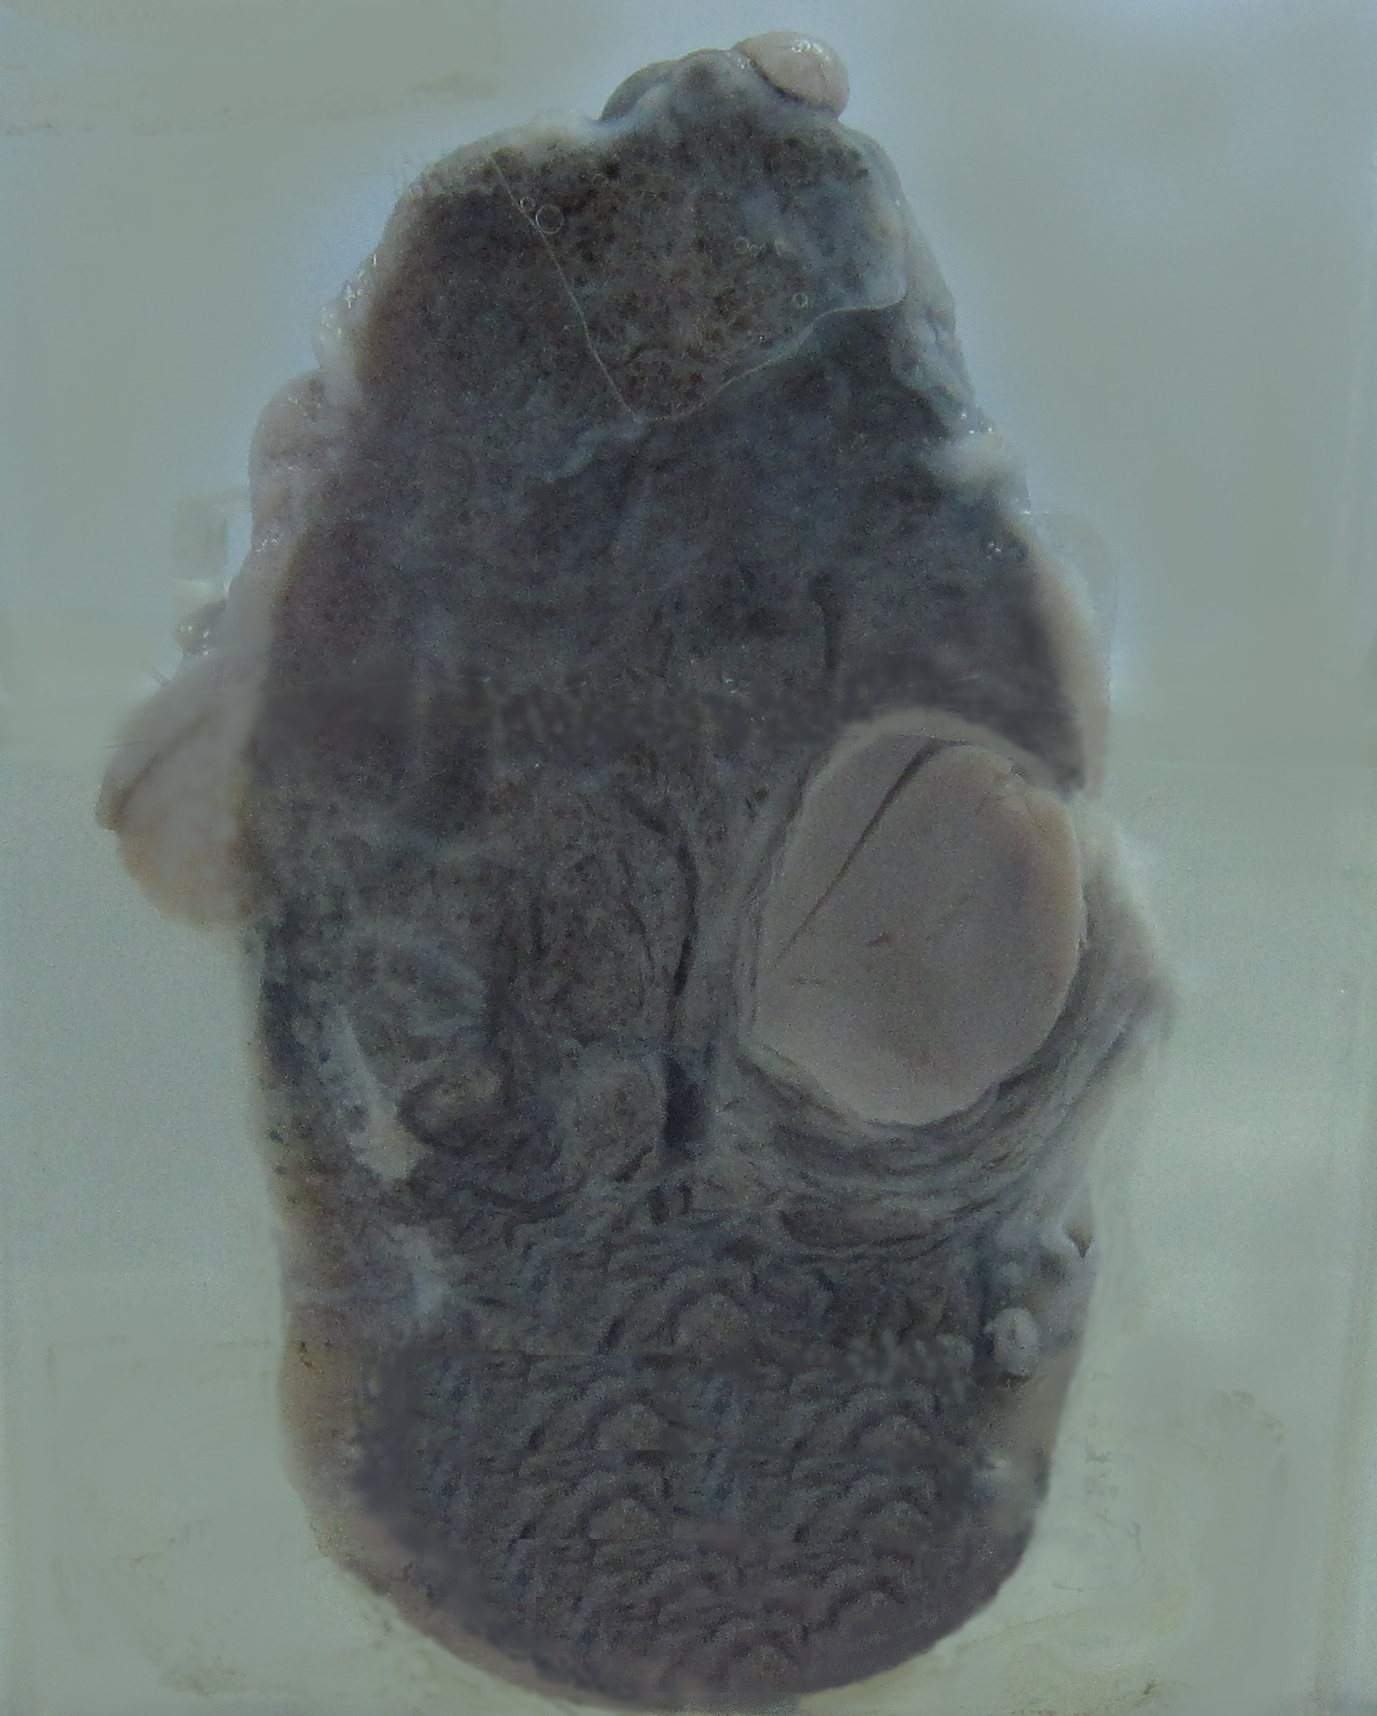

4.甲状腺腺瘤